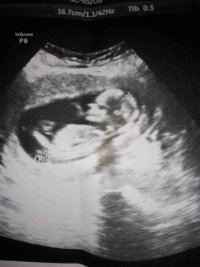

Bizede bakin bu gun verildi doktorumuz erkek dediMerhaba ,

Nub teorisiyle cinsiyeti uzman hekimler belirleyebiliyormuş. Bu yüzden doğruluk payı var.